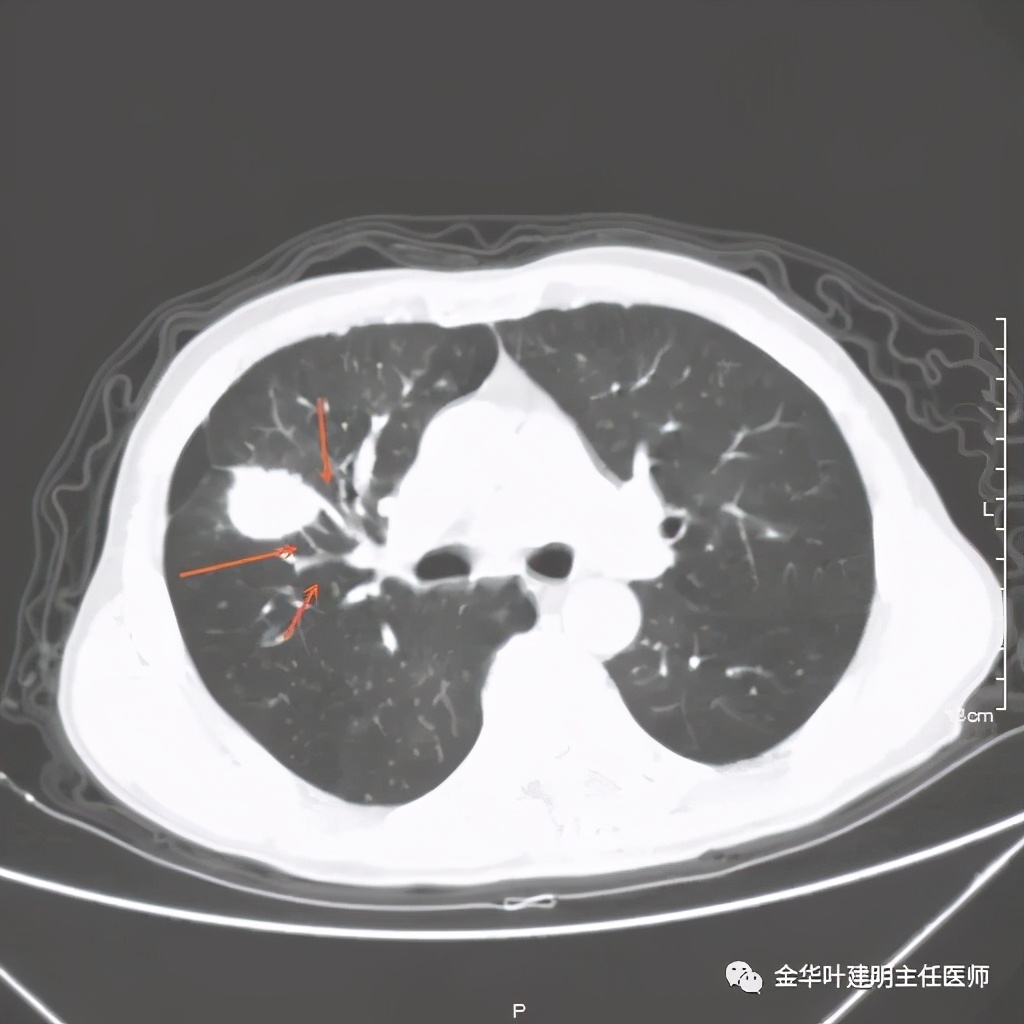

上图示病灶边缘不太光整,内部密度不太均匀

上图紫色箭头示叶间胸膜受牵拉,病灶边缘部分见到细毛刺

上图是穿刺时的某个层面,病灶的细毛刺征比较明显(蓝色箭头),病灶的边缘是不平的,而且有细短的毛刺样突向周围肺组织,这可是恶性的特征

上图也见细毛刺,但不是特别广的范围,有的边缘还是相对比较光滑了点

从影像的细节上看,有许多的影像表现是恶性的征象,这样的病灶我是认为必定恶性的,即使肺穿刺阴性!应该是假阴性,或者说,肺穿刺活检阴性并不足以让我认为它可排除肺癌,而是高度怀疑该阴性是假阴性。仍强烈建议手术切除,可以直接做肺叶切除并清扫淋巴结。患方接受了我的建议,头天刚办理出院的,次日又到我们科办理了住院手续。完善相关检查后,我们很快为其进行了“单孔胸腔镜下右上叶切除及淋巴结清扫术”,手术顺利,术后大体肉眼看就是典型的肺癌,中间坏死空洞,肿瘤质硬,收缩力强,表面不平,切面鱼肉样。术后病理确认是浸润性腺癌,下面是石蜡病理报告: